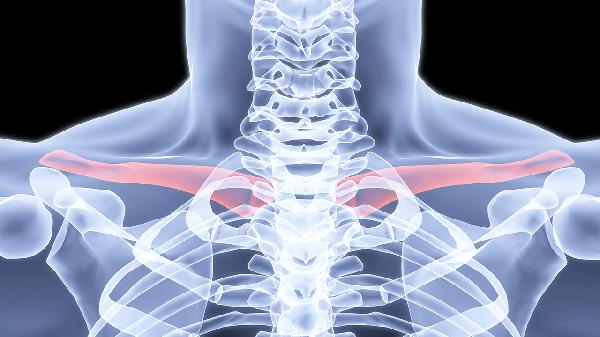

锁骨下面的骨头突出可能与锁骨本身、第一肋骨或胸骨异常有关,常见原因包括先天性发育异常、外伤后畸形愈合、营养不良性骨病以及胸廓出口综合征等。建议及时就医检查,明确诊断后针对性处理。

先天性发育异常可能导致锁骨或肋骨形态异常,表现为局部骨性突起。这类情况通常自幼存在,若未伴随血管神经压迫症状可暂不处理,但需定期复查观察变化。外伤后锁骨骨折畸形愈合是常见诱因,尤其见于青少年锁骨中段骨折后过度骨痂形成,可通过三维CT重建评估愈合情况,严重畸形影响功能时需手术矫正。

营养不良如维生素D缺乏性佝偻病可致肋骨串珠样改变,儿童患者可能伴随方颅、O型腿等体征,需补充维生素D3滴剂并增加日照。胸廓出口综合征患者可能因颈肋或第一肋骨异常压迫臂丛神经,出现上肢麻木疼痛,可通过神经电生理检查确诊,轻者采用康复训练,重者需行颈肋切除术。